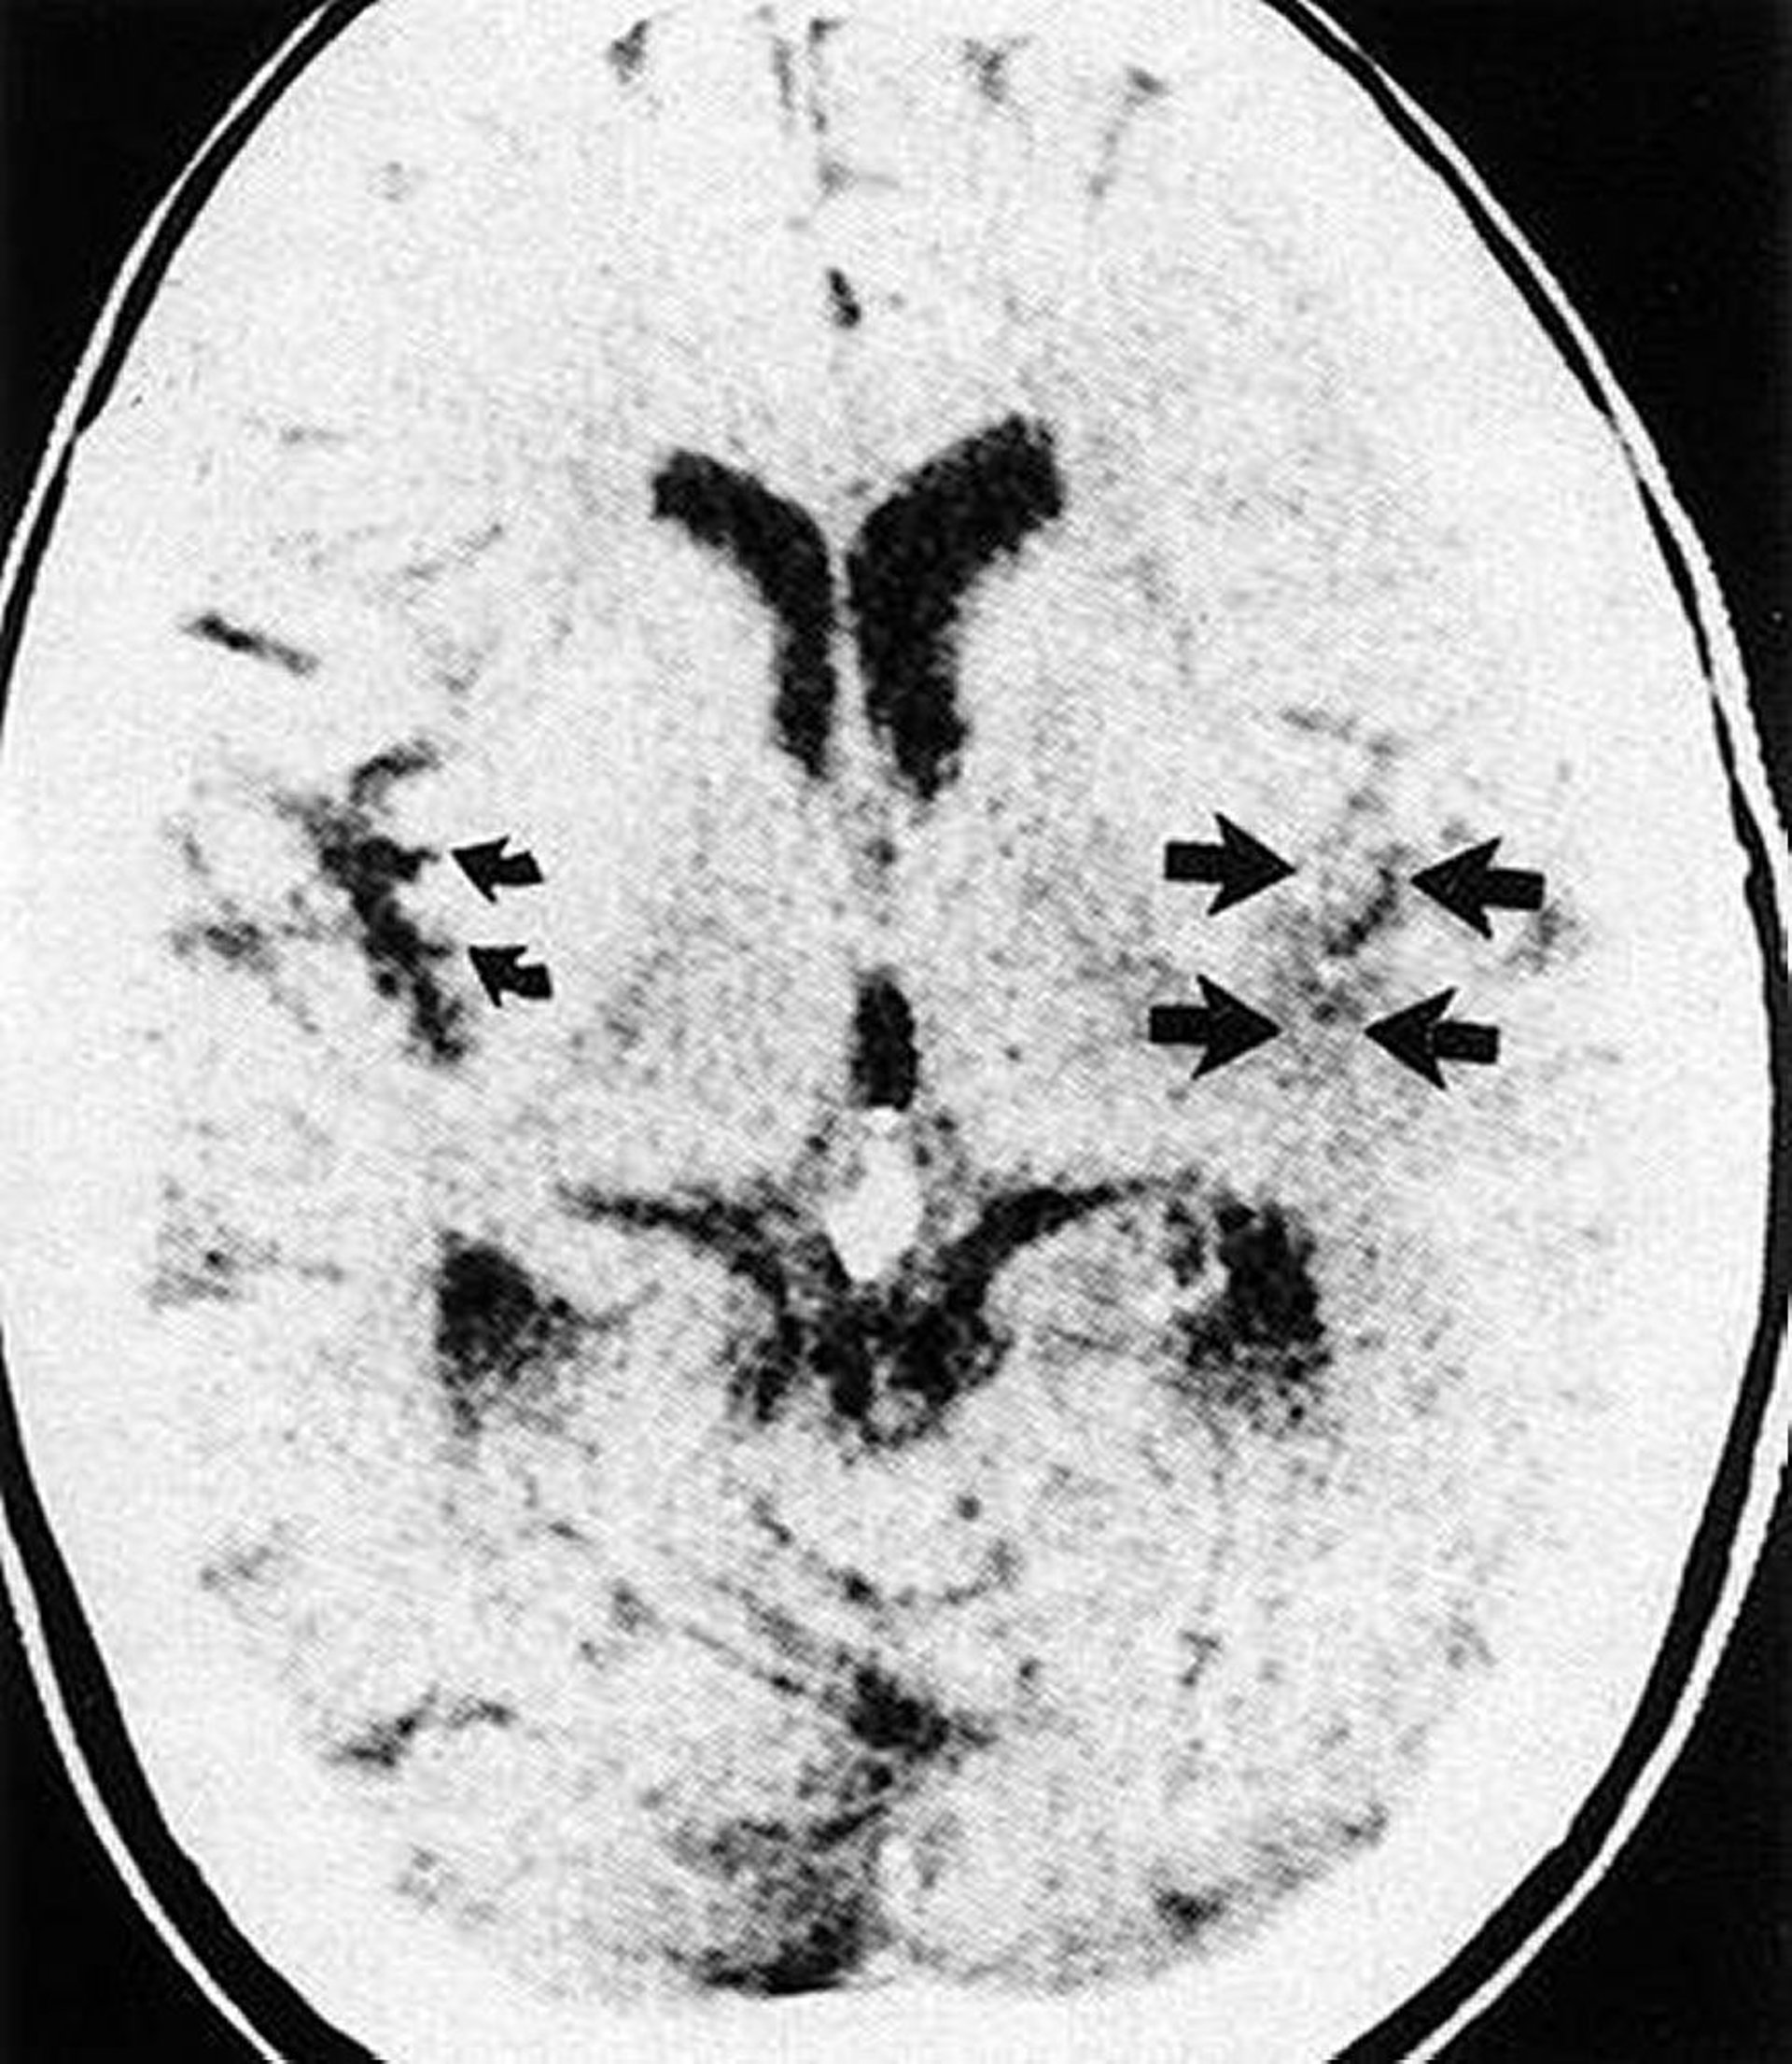

Esta TC muestra el borramiento de la cisura de Silvio y la cinta insular (flechas rectas) en el lado infartado del cerebro en comparación con la cinta insular normal (flechas curvas).

By permission of the publisher. From Geremia G, Greenlee W. In Atlas of Cerebrovascular Disease. Edited by PB Gorelick and MA Sloan. Philadelphia, Current Medicine, 1996.